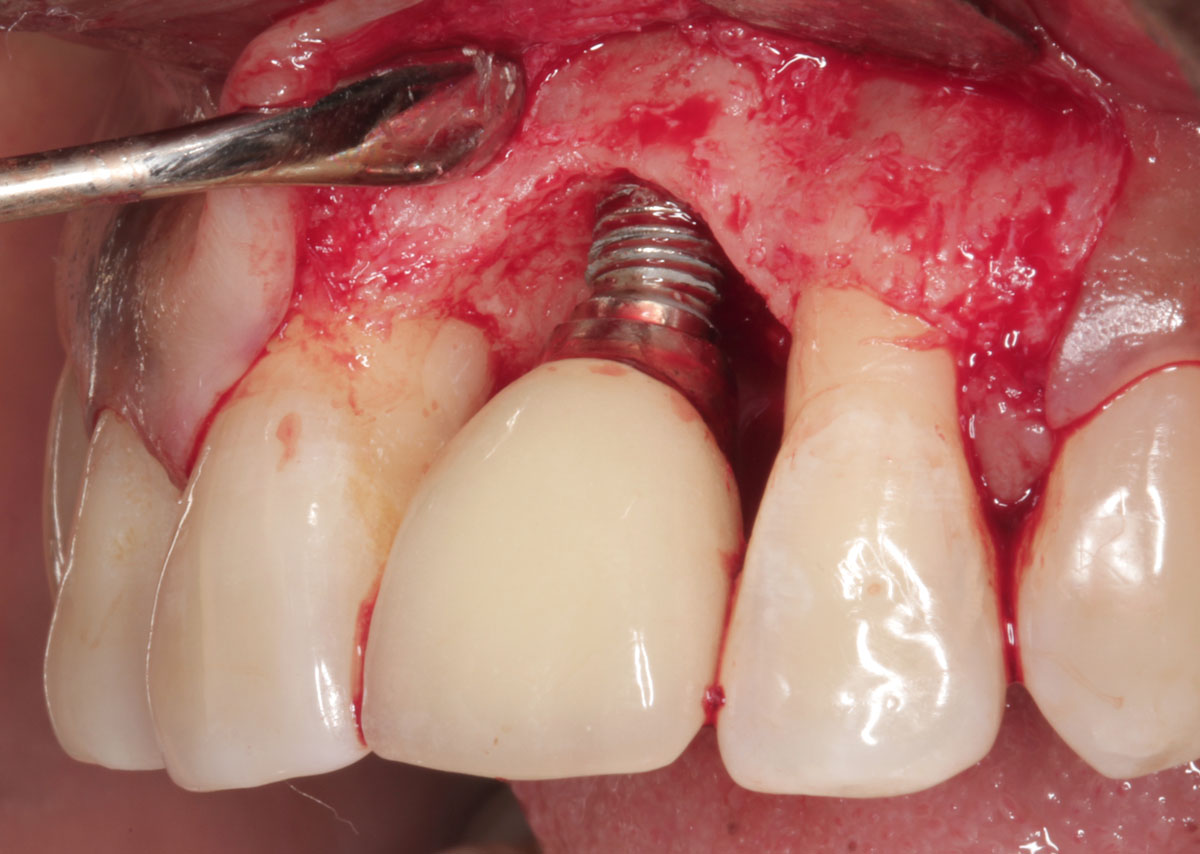

Por su parte, la periimplantitis se produce cuando a la inflamación de los tejidos blandos se le une a la de los tejidos duros. En este caso, sí puede estar en peligro el hueso que sujeta al implante y, además, puede producir problemas estéticos como la recesión de las encías o la pérdida del implante afectado si no se aplica un tratamiento a tiempo.

La mucositis perimplantaria es una enfermedad producida cuando los tejidos blandos que rodean al implante se inflaman.

Esta patología, habitual en personas con implantes, es reversible y no supone la pérdida del hueso.